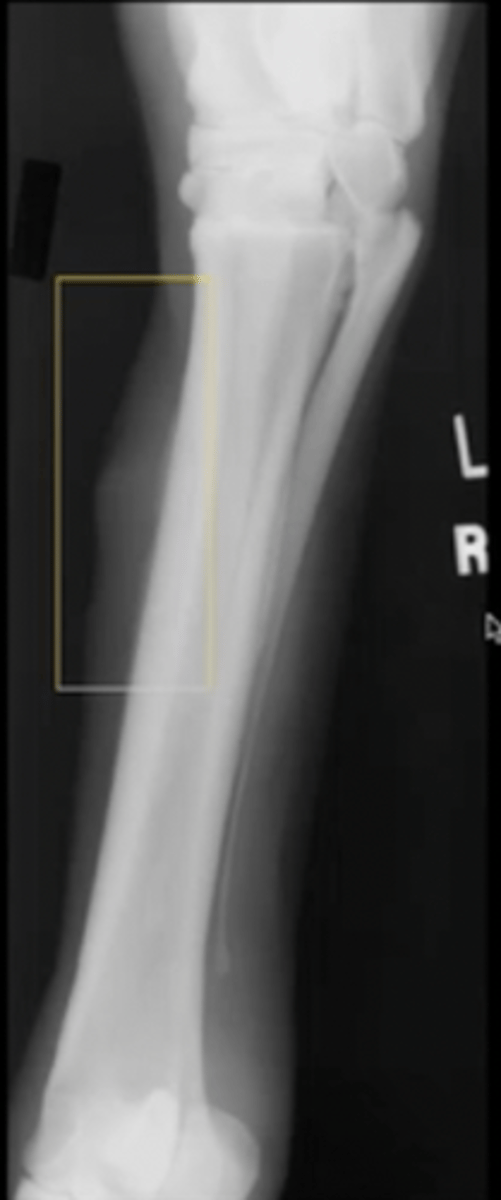

1.) smooth, lamellar

2.) pallisading

Two types of new bone formation

smooth, lamellar

What type of new bone formation is this?

pallisading